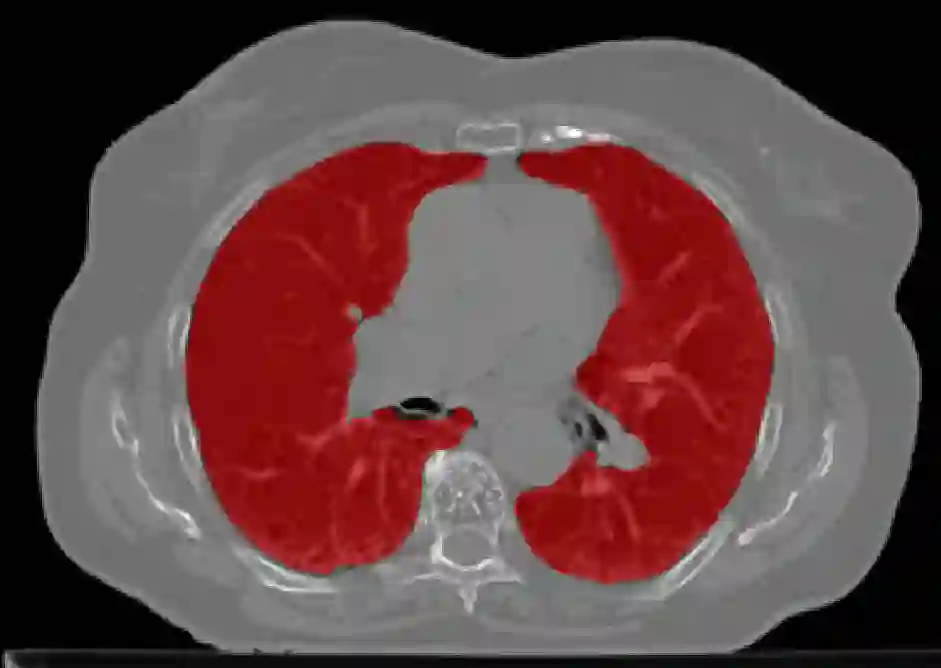

The COVID-19 pandemic has had a considerable impact on day-to-day life. Tackling the disease by providing the necessary resources to the affected is of paramount importance. However, estimation of the required resources is not a trivial task given the number of factors which determine the requirement. This issue can be addressed by predicting the probability that an infected patient requires Intensive Care Unit (ICU) support and the importance of each of the factors that influence it. Moreover, to assist the doctors in determining the patients at high risk of fatality, the probability of death is also calculated. For determining both the patient outcomes (ICU admission and death), a novel methodology is proposed by combining multi-modal features, extracted from Computed Tomography (CT) scans and Electronic Health Record (EHR) data. Deep learning models are leveraged to extract quantitative features from CT scans. These features combined with those directly read from the EHR database are fed into machine learning models to eventually output the probabilities of patient outcomes. This work demonstrates both the ability to apply a broad set of deep learning methods for general quantification of Chest CT scans and the ability to link these quantitative metrics to patient outcomes. The effectiveness of the proposed method is shown by testing it on an internally curated dataset, achieving a mean area under Receiver operating characteristic curve (AUC) of 0.77 on ICU admission prediction and a mean AUC of 0.73 on death prediction using the best performing classifiers.